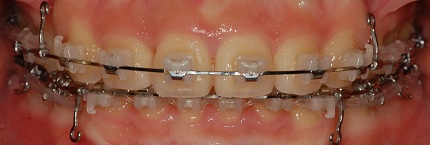

정면 사진